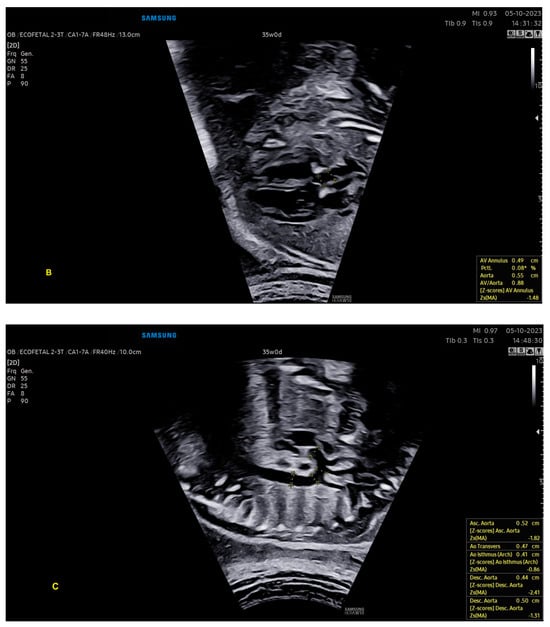

With ML, the ultrasound machine is able to automatically obtain cardiac measurements based on the identification of anatomical cardiac structures, reducing the scan time and inter-observer measurement variation. In this scenario, not only anatomical, but also functional parameters (such as the myocardial performance index) can be automatically measured. With the advances in AI, this technology has been increasingly added to ultrasound devices, such as obstetric ultrasound, and is applicable to three areas: structure identification, automatic measurements, and the classification of diagnosis. AI software (Heart Assist and MPI+—Samsung Healthcare, Gangwon, South Korea) can identify the fetal heart structures and perform automatic biometric and the right and left myocardial performance index measurements, respectively (Figure 12 and Figure 13) [42,43,44].

Figure 12.

Artificial Intelligence (Heart Assistance). The cardiac ultrasound device is able to recognize anatomical heart structures and perform automatic measurements: (A) ventricles (width of atria and ventricles); (B) left ventricular outflow tract (atrioventricular annulus and ascending aorta); (C) aorta in sagittal view (ascending, transverse, isthmus, and descending aortas). Note that the images include the z-scores of these structures, which were also calculated automatically. LV: left ventricle; LA: left atrium; RA: right atrium; RV: right ventricle; Asc. aorta: ascending aorta; Desc. aorta: descending aorta; Transvers. aorta: transverse aorta.